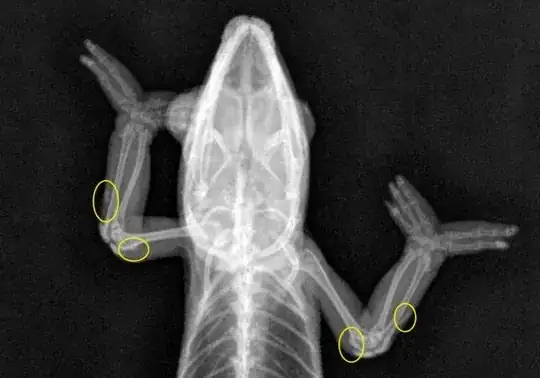

Here is an X-Ray of a chameleon with gout, the owner caught it pretty early on, so it's not so well defined in the X-Rays, but it give's you an idea of what you're looking at.

(Source)